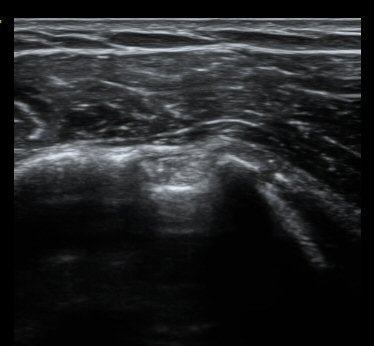

ȸÀü±Ù°³°£°Ý Ⱦ´Ü¸é°Ë»ç¿¡¼­ Á¡¾×³¶³» ¼ö¾×Àú·ù°¡ °üÂûµÈ´Ù(±×¸² 1). ÀÌµÎ¹Ú±Ù°Ç °í¶û¿¡¼­´Â ƯÀÌ ¼Ò°ßÀ» º¸ÀÌÁö ¾Ê´Â´Ù(±×¸² 2). ȸÀü±Ù°³°£°Ý ³»Ãø¿¡¼­ °ß°©ÇϱٰÇÀÇ ÆÄ¿­°ú Á¡¾×³¶³» ¼ö¾×Àú·ù°¡ °üÂûµÈ´Ù(±×¸² 3, 4). ±Ø»ó°Ç Ⱦ´Ü